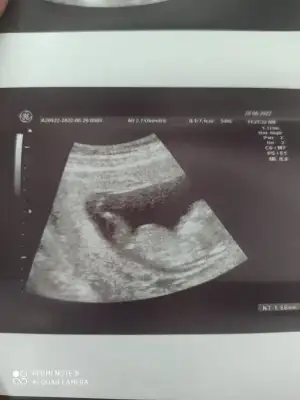

Karından ilki bir aylık diğeri üç yâda iki

• IMG_20220519_212815.webp

IMG_20220519_212815.webp

24,8 KB · Görüntüleme: 85